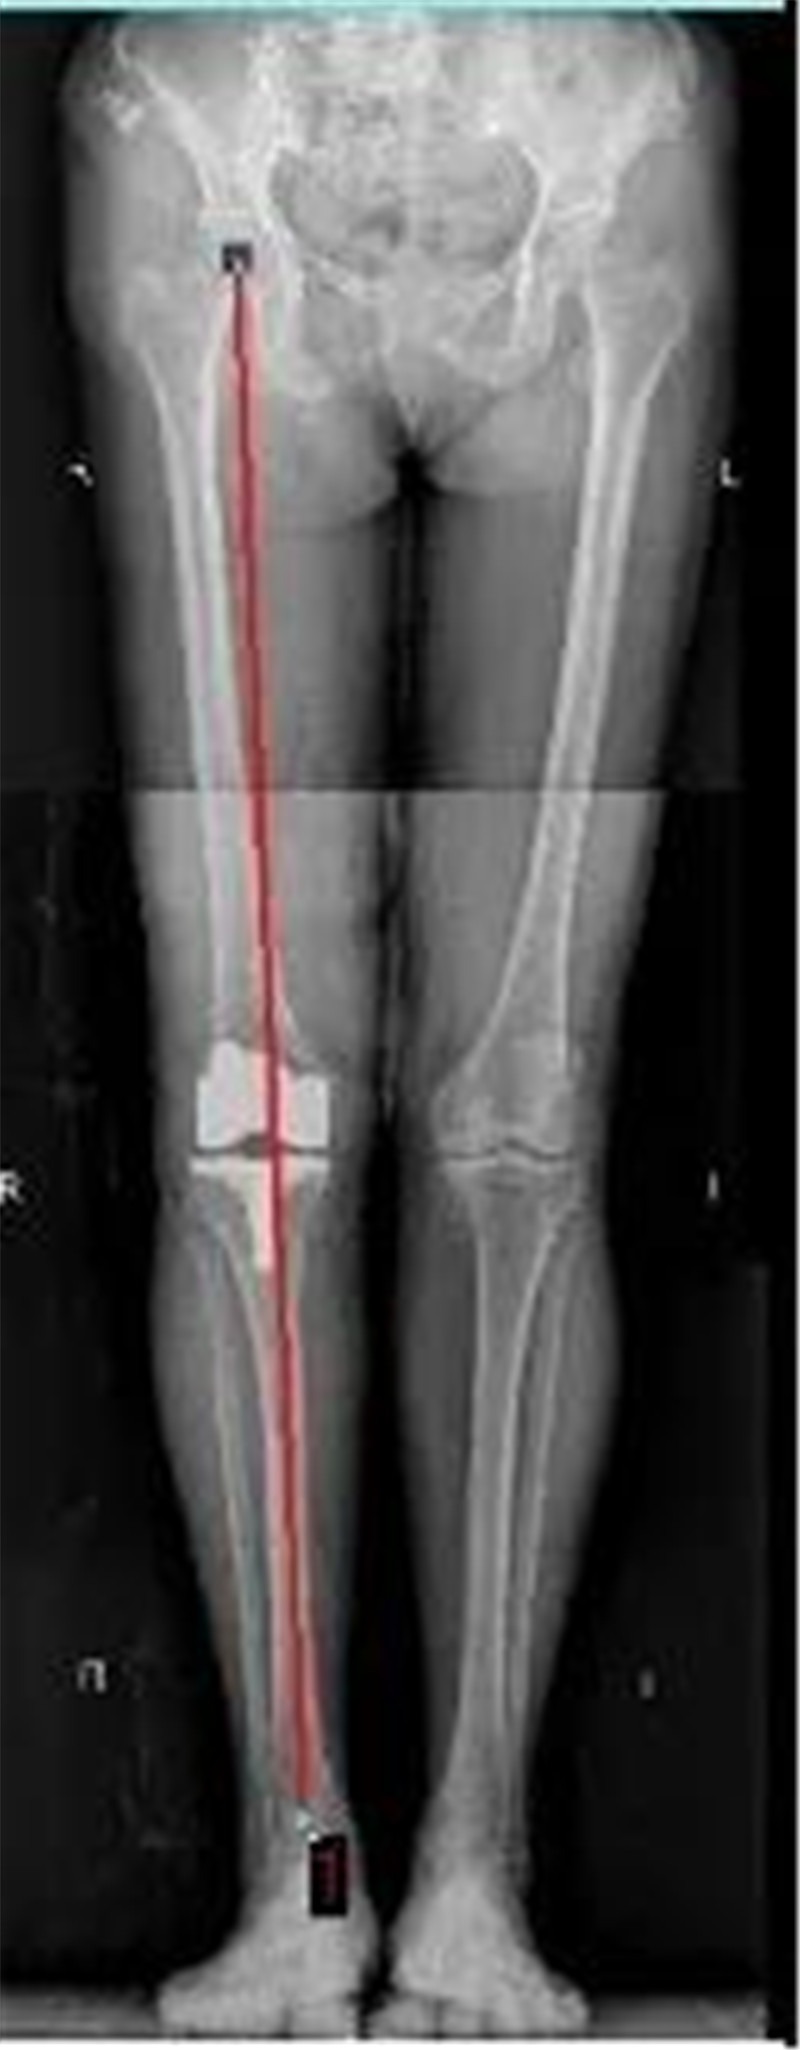

5月7日,我院脊柱关节外科主任潘磊博士为李阿姨进行了“膝关节表面置换术”,通过医学影像可以看到李阿姨右膝关节磨损非常严重,并且出现了严重的外翻畸形(外八字),潘主任医生团队通过进行一个类似“镶牙”一样的手术,把增生老化的关节表面去除后装上合适的人工关节,一个小时左右手术顺利完成。术后医生每天查房指导李阿姨和陈阿姨进行康复练习。

X型腿矫正对比